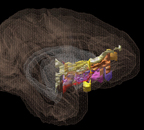

Rules for prefrontal cortical pathways: how they really get their targets: 2.1 Rules for the ventral prefrontal cortex Rules- vmPFC cortical & subcortical pathways. OFC cortical & subcortical pathways; 2.2 Monkey and Human ventral prefrontal fibers use the same organizational rules DTI; 2.3 The cingulate bundle carries more than you think Cingulate; 2.4 Internal capsule: an organized gateway for connections Internal capsule.